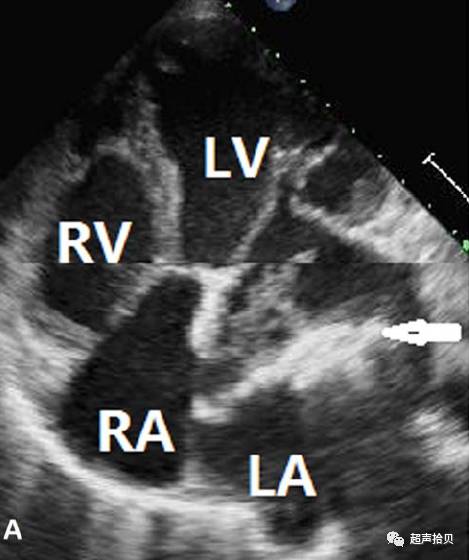

病例3:粘液瘤伴严重钙化

案例3一51岁男性出现劳力性呼吸困难、胸闷,并在1个月内两次咯血。体检发现36.88c体温,108 BPM的心率,3级/ 6心尖收缩期杂音,并以双下肢胫前水肿。经胸超声心动图显示左心房和左心室扩

张,形成一个巨大的、不规则的、钙化的肿块,如图3所示。57 3 40毫米),附在左心房中隔,占据了左心房容积1/3;肿块大部分伴有强回声钙化(图3A和视频4)。患者左心室射血分数为57%。他有严重的二尖瓣返流(图3b和录像5),中度三尖瓣返流和中度肺动脉高压。心电图显示心房颤动。超声显示左小腿静脉有血栓。血液检测显示脑钠素和血浆d-二聚体分别为536和1.36毫克/升。肺动脉CT血管造影显示肺动脉主干及其分支部分伴有肺动脉血栓。

仔细检查,医生发现了7年的左心房肿瘤医疗记录病史。肿块体积逐年增大,二尖瓣功能受到明显影响。切除标本显示一个黄色的真石漆的肿块,伴有大多数肿瘤钙化(图3c)。二尖瓣小叶弥漫性增厚,在术前超声心动图检查中未发现后叶P3段的大穿孔。漏诊的原因可能粘液瘤钙化影响粘液瘤二尖瓣穿孔的观察,所有的腱索增厚,与二尖瓣环直径明显扩张。病人接受了粘液瘤切除术和二尖瓣成形术。组织病理检查发现左心房粘液瘤广泛钙化(图3),